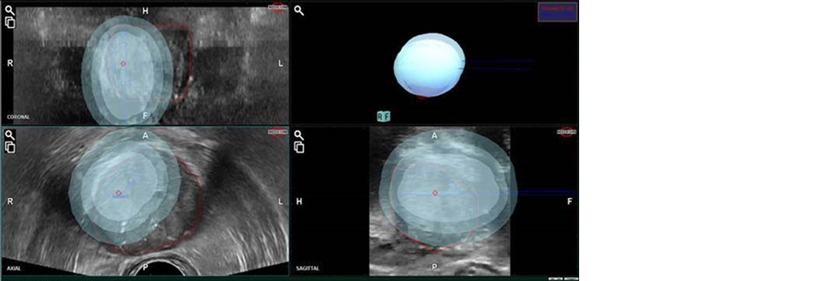

ARIETTA 65 IntuitiveFusion can store and export datasets to Focal Therapy planning software such as cryotherapy, high-intensity focused ultrasound (HIFU), and brachytherapy. For Cryotherapy, it is possible to display a simulation of the temperature distribution of the target area*1. It is also useful for treatment monitoring and active surveillance.

Cryotherapy zones: display of temperature distribution curves*1